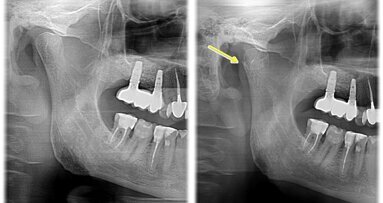

BUDAPESZT, Węgry: Sztuczna inteligencja (AI) szybko i radykalnie zmienia branżę stomatologiczną, a jej wpływ jest szczególnie widoczny w diagnostyce, gdzie platformy oparte na sztucznej inteligencji są w stanie szybko i skutecznie analizować szeroki zakres informacji wizualnych w celu rozpoznania różnorodnych patologii jamy ustnej. Aby ocenić dokładność modeli sztucznej inteligencji w wykrywaniu próchnicy w oparciu o zdjęcia rentgenowskie (skrzydłowo-zgryzowe), naukowcy z Uniwersytetu Semmelweis w Budapeszcie przeprowadzili przegląd systematyczny i metaanalizę badań na temat tych metod. Uzyskane wyniki potwierdzają przekonanie, że modele sztucznej inteligencji mogą być bardzo przydatne i skuteczne w warunkach klinicznych, ale nadal to czynnik ludzki, czyli w tym wypadku lekarz dentysta, pozostaje kluczowym elementem do ostatecznej oceny i diagnozy.

Wyniki badania ujawniły bardzo wysoką dokładność diagnostyczną sztucznej inteligencji. Łączna czułość wyniosła 94%, a swoistość 91%, co pokazuje zdolność sztucznej inteligencji do wykrywania zmian próchnicowych i skutecznego wykluczania zdrowych zębów. Modele wykazały wysokie ujemne wartości predykcyjne, co sugeruje niezawodność sztucznej inteligencji w identyfikowaniu przypadków innych niż próchnica, chociaż dodatnie wartości predykcyjne były umiarkowane, co wskazywało na możliwość nieprawidłowego identyfikowania zdrowych zębów jako próchnicowych. Diagnostyczny iloraz szans, który określa, o ile bardziej prawdopodobne jest, że ząb z próchnicą zostanie oznaczony jako „zepsuty”, w porównaniu ze zdrowym zębem, był wysoki, co jeszcze bardziej podkreśliło prawidłowe działanie sztucznej inteligencji, zwłaszcza w porównaniu z ekspertami, których czułość została stwierdzona w innych badaniach zwykle opóźnia się na poziomie 24–36%, chociaż ich swoistość jest wysoka i wynosi 94–97%. W tej metaanalizie nie można było porównać trafności diagnostycznej sztucznej inteligencji z ekspertami ze względu na brak danych opublikowanych w uwzględnionych badaniach.

Klinicznie implikacje stosowania sztucznej inteligencji są znaczące. Sztuczna inteligencja może zaoferować istotną pomoc w wykrywaniu próchnicy; w badaniu podkreślono jednak konieczność nadzoru i weryfikacji w celu potwierdzenia pozytywnych wyników, aby zapobiec niepotrzebnemu leczeniu lub błędnym diagnozom. Uzupełniając wiedzę ludzką, sztuczna inteligencja może usprawnić przepływ pracy w gabinecie dentystycznym, zwiększyć precyzję diagnostyki, nie zastąpi jednak specjalisty.